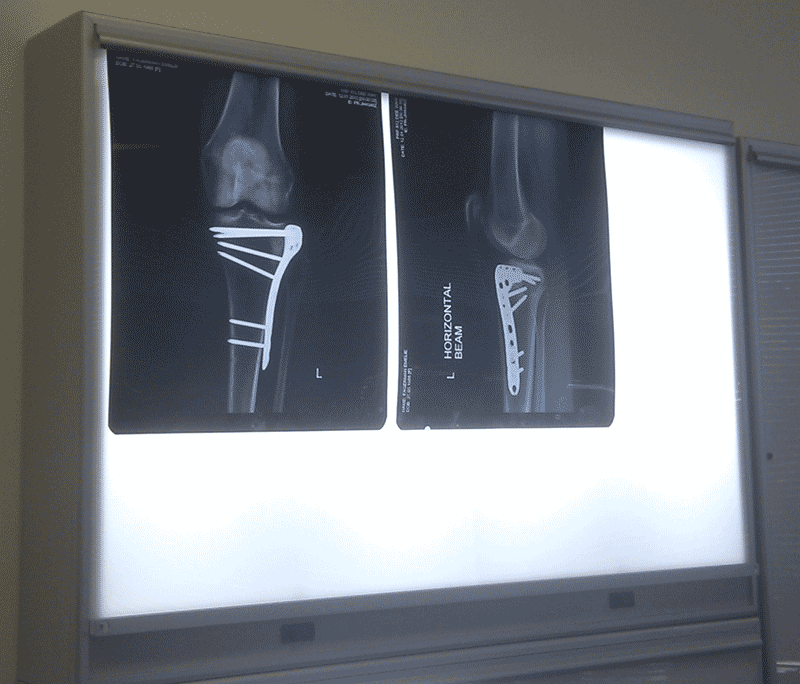

x-ray kneeSom några av er vet klämde min lillasyster sitt knä mellan två bilar i december. Länge var det tal om att de skulle ta ben från hennes höft för att laga henne, istället sitter det nu en massa metall i knät. Emelie visade stolt upp sina röntgenbilder för mig och jag tycker att det ser ut som om farbror doktor glömt kvar sina redskap i henne, eller så har en alien bosatt sig i hennes knä… Vilket är mest troligt?

Elchocker på knäOperationen var strax efter jul och hon började äntligen att jobba denna veckan efter att ha varit sjukskriven ett tag. För att få igång knät så går hon regelbundet till sjukgymnasten. En av behandlingarna är en typ av elchock som sätts på knät för att få igång blodcirkulationen. Men det är ju mycket roligare att säga att Emelie får elchocker 😀